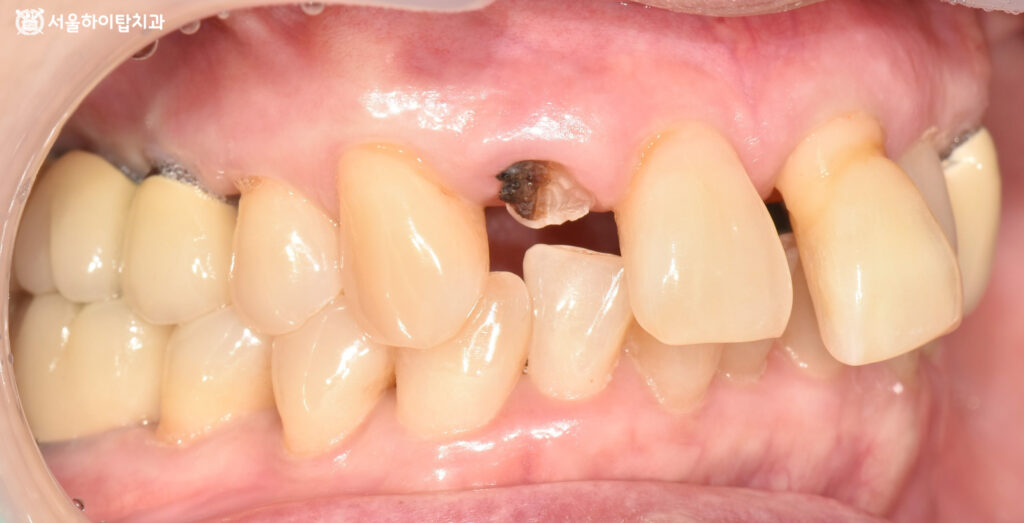

1. 초진

만수동 치과 에서 표시한 부분을 보면,

부러진 자연치와 일부 정출된

모습을 확인할 수 있습니다.

이러한 문제가 동시에 나타난 이유는,

충치로 인한 치질 약화와 골 소실이

함께 진행되었기 때문입니다.

이에 따라 구강 내 사진을 보면

충치로 인해 부러진 파절면이

뚜렷하게 관찰됩니다.

또한 뼈의 흡수로 인해

정출되고 앞니 사이가 벌어진